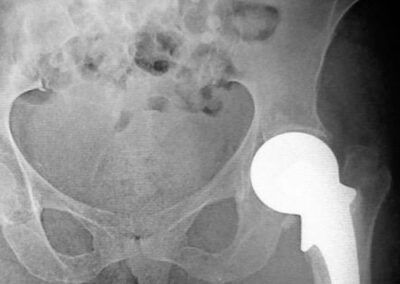

Exemplos de artroplastia cimentada e não-cimentada podem ser vistos na Fig. 2, através das radiografias. A figura ainda mostra exemplos radiográficos de artroplastias híbrida (haste femoral cimentada e componente acetabular não-cimentado) e híbrida-reversa (haste femoral não-cimentada e componente acetabular cimentado). O sucesso da artroplastia total de quadril depende basicamente de três fatores críticos: escolha do paciente, do implante e da técnica cirúrgica. Provavelmente, o determinante isolado mais importante seja a escolha apropriada do paciente. A escolha de um paciente inadequado pode comprometer o design mais avançado ou mesmo o cirurgião mais experiente (1,2,7).